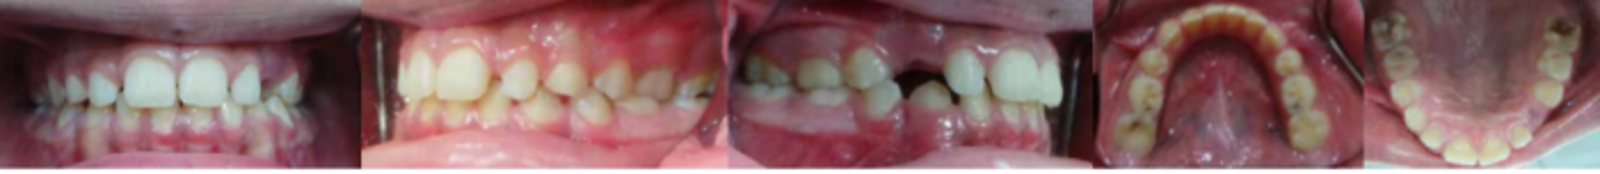

MIH was diagnosed based on clinical appearance. See Figures 1 (a, b, c, d & e) for clinical features. Figures 2 (a, b & c) for radiographic findings.A diagnostic list and treatment plan was formulated by a specialist of Paediatric dentist as well as orthodontist and explained in detailed to the father.

Fig. 1 (a, b, c, d & e). Showing a dislodged filling of 36. 16 yellowish brown hypomineralised lesions. 36 and46 large composite fillings.